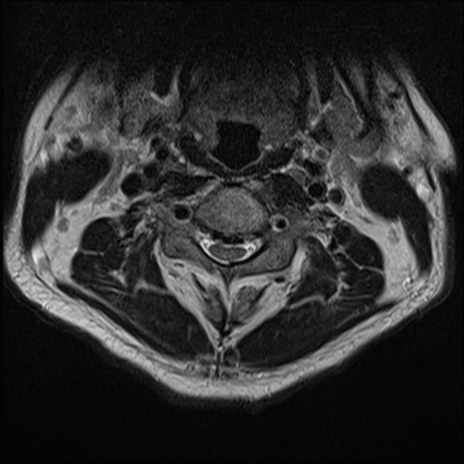

【整形】TIPS症例7 頚椎MRI T2WI(横断像)

頚椎MRI

矢状断像と横断像